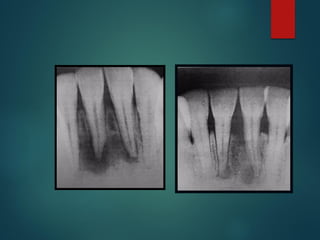

Clasificación Radiográfica

De Las Caries

 Incipiente de esmalte

 De esmalte

 Dentinaria superficial

 Dentinaria profunda

 Sobreproyectada en cámara pulpar

 Penetrante